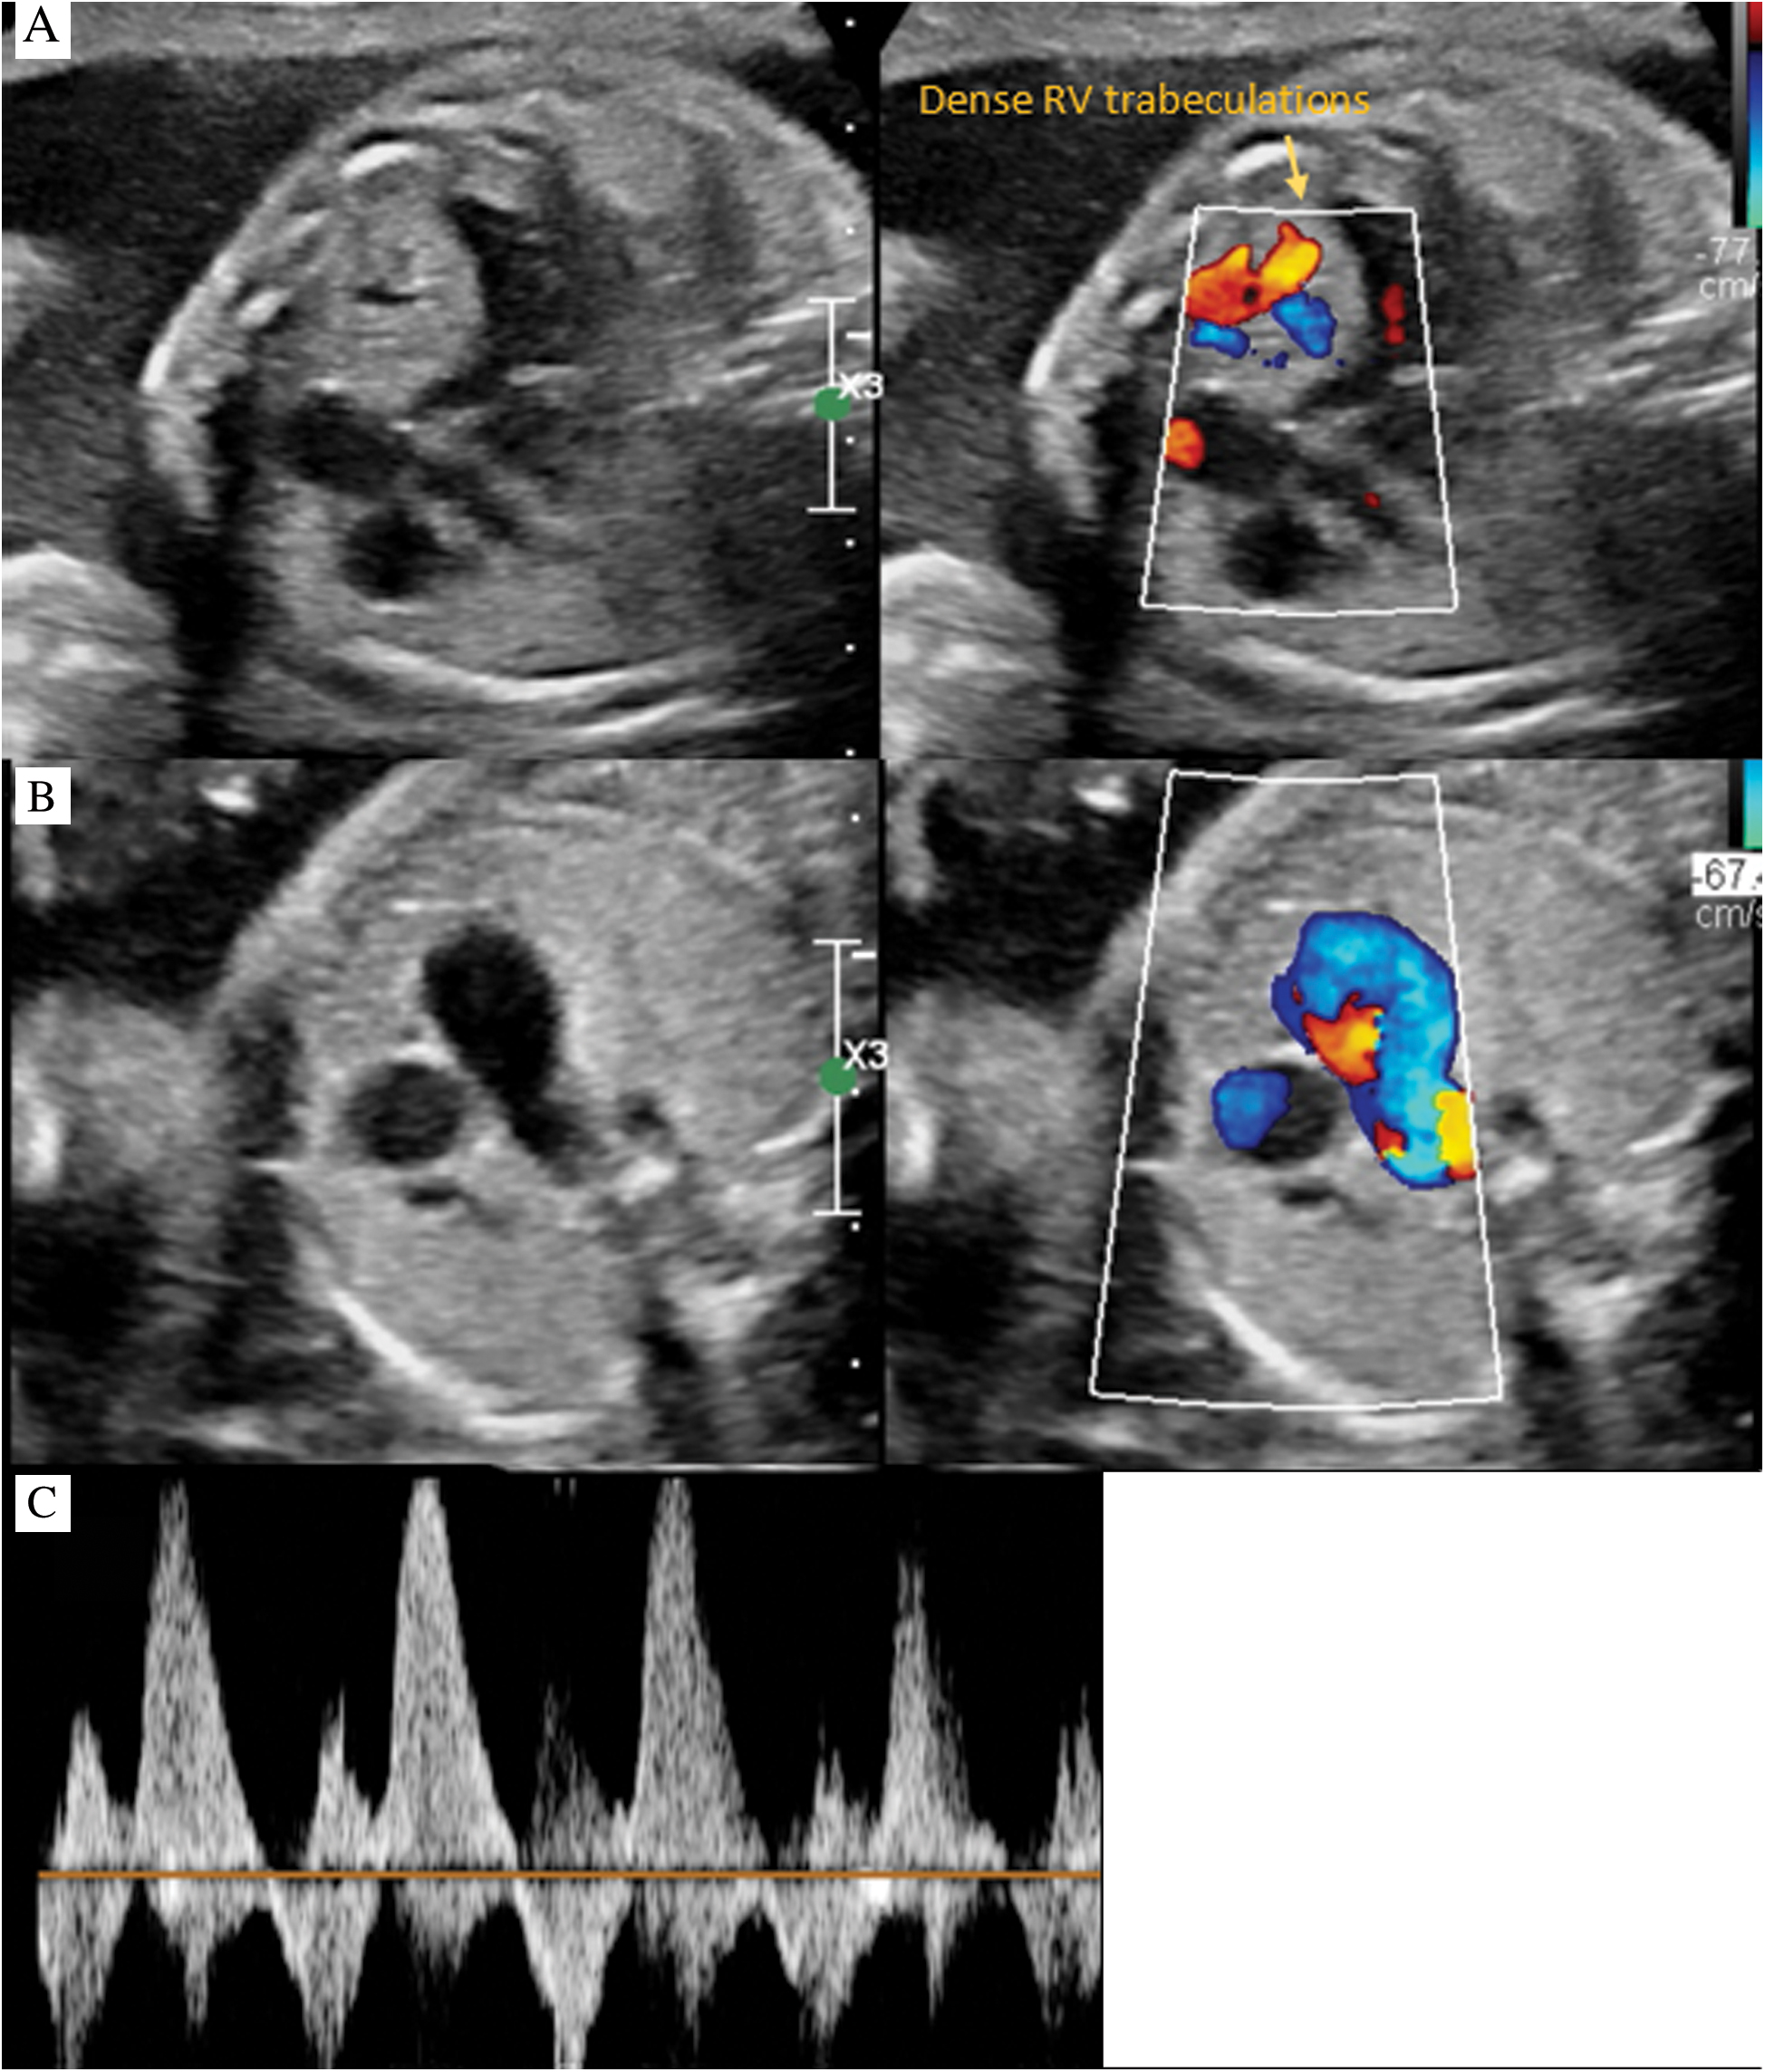

At 24 weeks gestation, a newborn male was prenatally diagnosed by fetal echocardiography to have severe RV hypertrophy with depressed function, aneurysmal dilation of the main pulmonary artery and tachyarrhythmia. The RV cavity was moderately hypoplastic with decrease tricuspid valve inflow (Fig. 1A), despite the appearance of adequate antegrade flow across the pulmonary valve. The hypertrophied interventricular septum appeared to bulge into the left ventricular (LV) outflow tract, without significant obstruction. The LV cavity retained normal dimensions and function. A tortuous ductus had bidirectional flow (Figs. 1B and 1C). There was aneurysmal dilation of the ascending aorta and main pulmonary artery. Some degree of hemodynamic compromise was evidenced by a small pericardial effusion around RV free wall, as well as abnormal ductus venosus and umbilical venous Doppler patterns.

Figure 1: Fetal echocardiography. A: Four chamber color compare with cardiomegaly, RV dysplasia and dense trabeculations. B: 3 vessel view color compare with bidirectional flow in MPA. C: Doppler interrogation of MPA demonstrating bidirectional flow